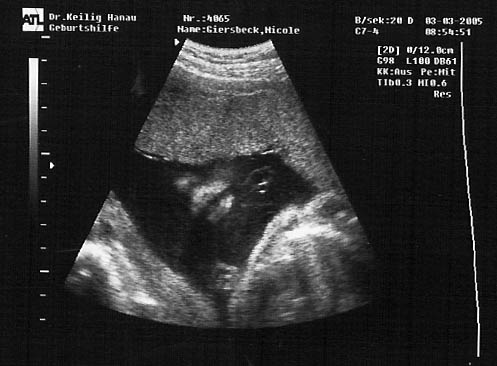

Meine Ultraschall-Bilder